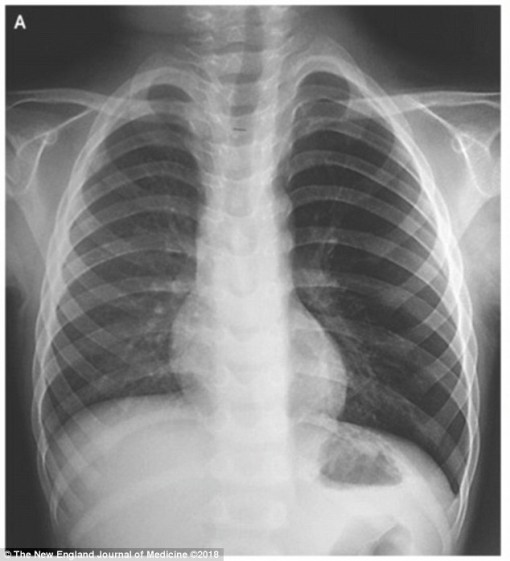

• Bé trai hít phải chiếc còi đồ chơi vào phổi

Bé trai hít phải chiếc còi đồ chơi vào phổi

12-08-2018 17:00

Chiếc còi đồ chơi kẹt trong phổi khiến bệnh nhi ho khan dai dẳng và phát ra tiếng rít lạ từ phổi.